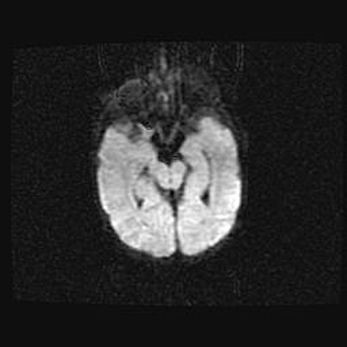

Множественные кисты обоих полушарий головного мозга, наибольшая из них в правой затылочной области. Ассиметричная атрофическая гидроцефалия.

Возраст: 7 месяцев

Вес: 5660 г

Пол: мужской

Окружность головы: 41,5 см

Срок гестации: 28-29 недель

Кисты головного мозга развиваются в результате многоочаговых некрозов вещества мозга и возникают вследствие перенесенной перинатальной инфекции, менингитов, энцефалитов, асфиксии, родовой травмы, расстройств мозгового кровообращения различного генеза. Образованию кист в веществе головного мозга плодов и новорожденных способствуют такие факторы, как высокое содержание в нем воды, недостаточная (или отсутствие) миелинизация и слабая астроглиальная реакция на повреждение.

Кисты могут сочетаться с гидроцефалией и другими поражениями головного мозга.